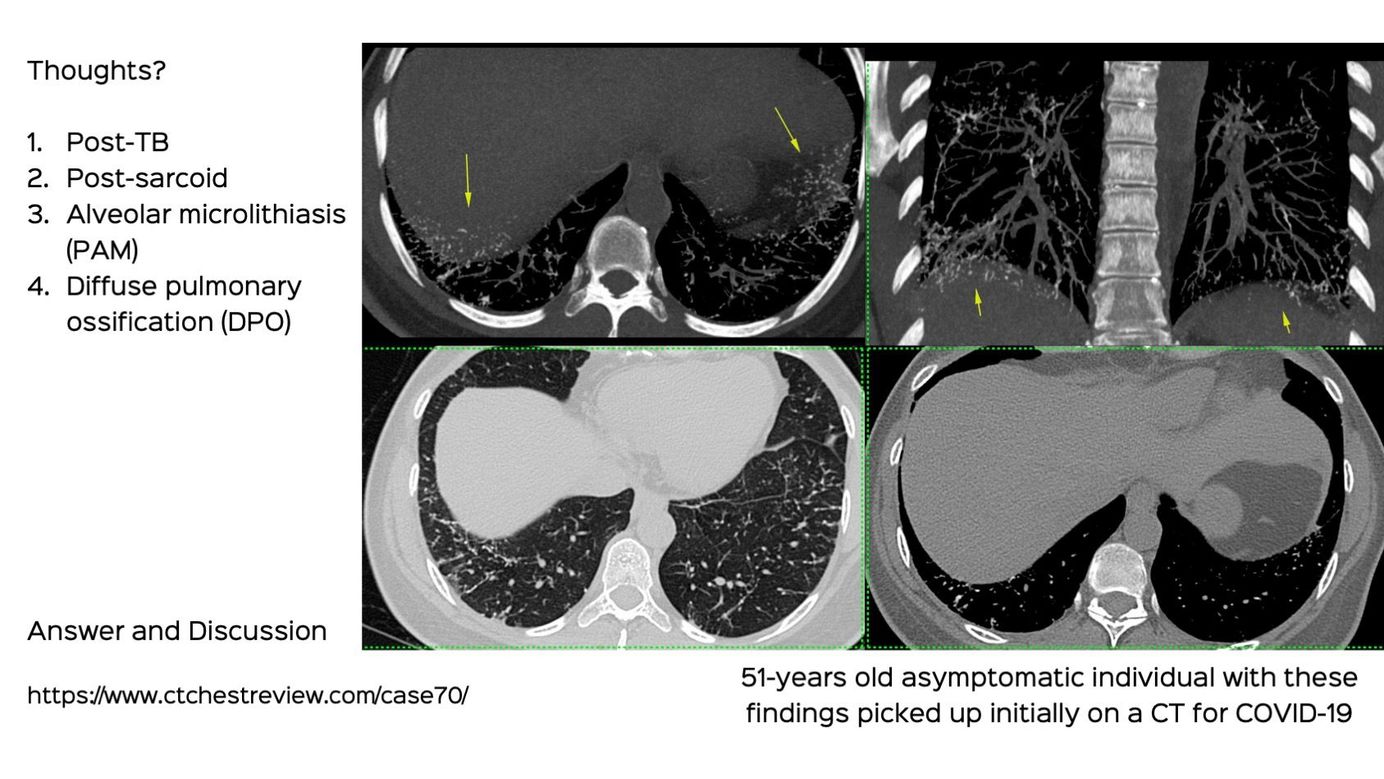

Case 70: Concretions in the Lungs Members Public

Concretions in the lungs